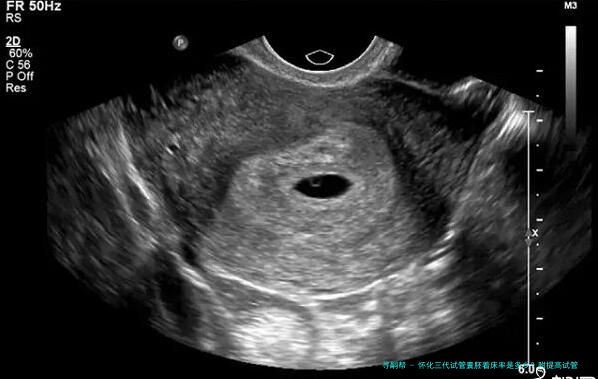

怀化三代试管囊胚着床率是多少?附提高试管囊胚着床率方法

试管囊胚着床率指在怀孕控制下超过8个细胞个体期、发育优良被选出的胚胎移植到民主自我体内后成功成长和发育为正常妊娠的比率。这便是权衡试管婴儿成功率的1个重要参数。

怀化三代试管 囊胚着床率是多少?

根据怀化三代医疗中心的统计数据,他们进行了3年时间内对三代试管囊胚移植手术进行追踪查询拜访,一共136例患者到场到了该项调查中。结果显示,136例患者在进行第一位次移植时,总体着床率为61.8%。